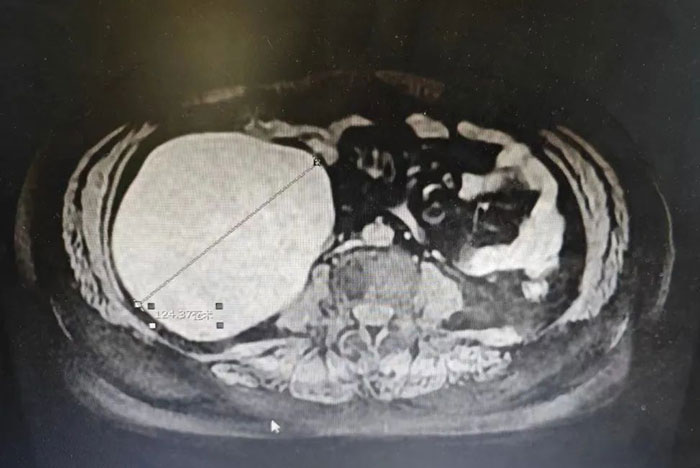

近日,滄州市中心醫(yī)院河間分院肝膽外科(外一科)、婦科、麻醉科通力合作共同協(xié)作成功為一女性患者切除將近13厘米大小的巨大腹膜后腫瘤,聯(lián)合右半結(jié)腸切除術(shù)。通過多學(xué)科協(xié)作治療,再次彰顯滄州市中心醫(yī)院河間分院外科技術(shù)實力。

患者腫瘤位于升結(jié)腸后方,體積巨大,上至結(jié)腸肝區(qū),下至盆腔入口處,擠壓升結(jié)腸向腹部正中內(nèi)側(cè)推移,質(zhì)地硬,有完整包膜,前方與升結(jié)腸系膜融合,未浸透漿膜層,無法分離。同時患者右側(cè)卵巢內(nèi)存在一個直徑5厘米的囊性腫物。

巨大腫瘤與輸尿管、生殖血管、及腸管密切相連,擠壓體內(nèi)多個臟器。在完整剝離巨大的腹膜后腫瘤和盆腔囊性腫物的基礎(chǔ)上,手術(shù)醫(yī)生還要做到保護周圍臟器、血管,減少患者出血量,這可謂是一項巨大的挑戰(zhàn)。